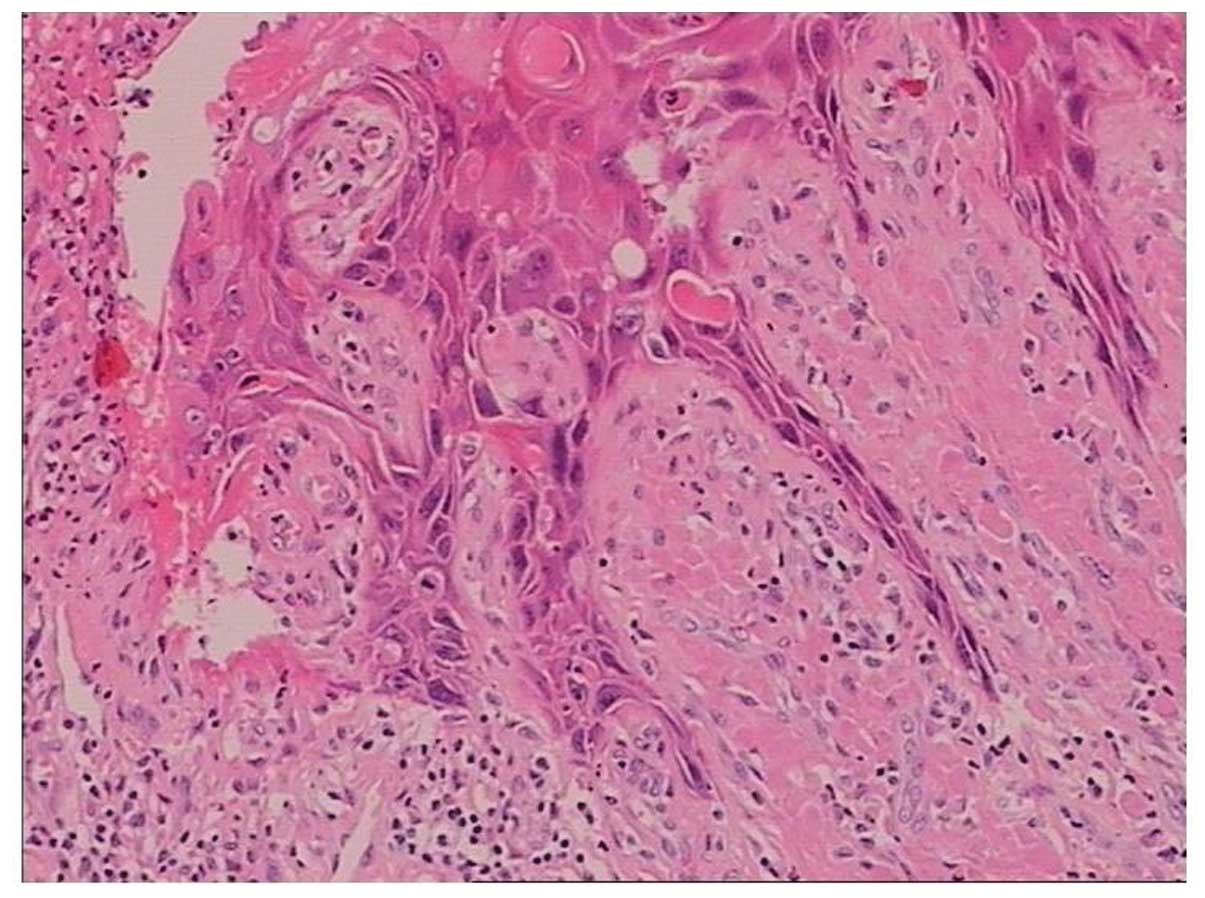

Симптомы кондилом могут варьироваться, и визуальное представление этого заболевания может быть различным. Некоторые кондиломы выглядят как небольшие бугорки или бородавки, в то время как другие могут иметь форму плоских пятен или цветных наростов.